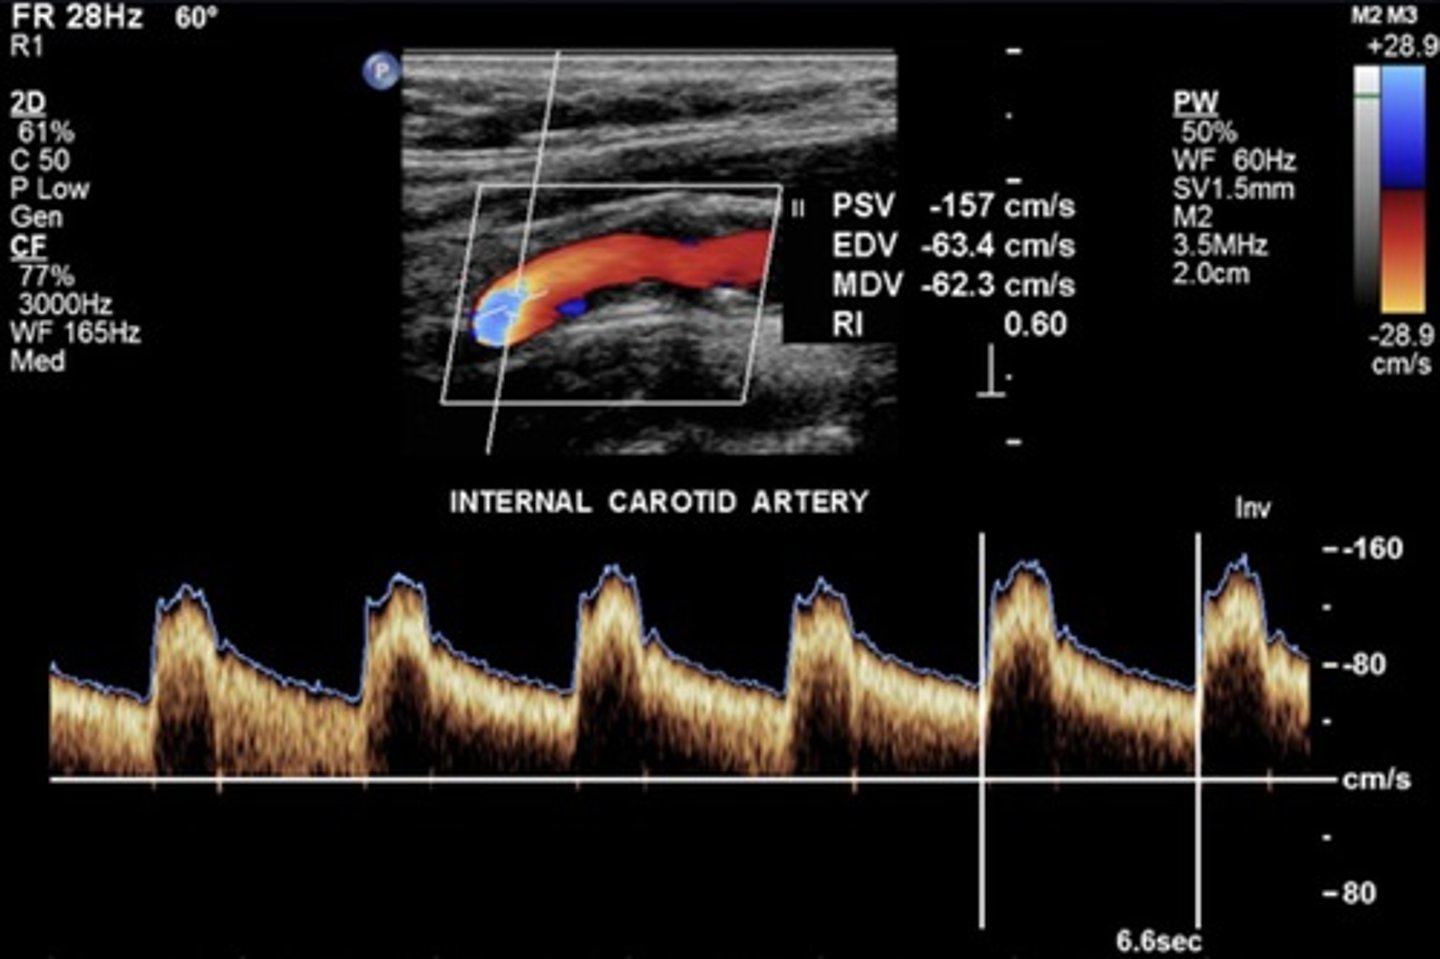

Normal ICA Waveform

Lowest resistance

Doppler Characteristics of Carotid A

Low resistant - except prox. CCA & ECA

High off baseline

Spectral window

Continuous forward flow